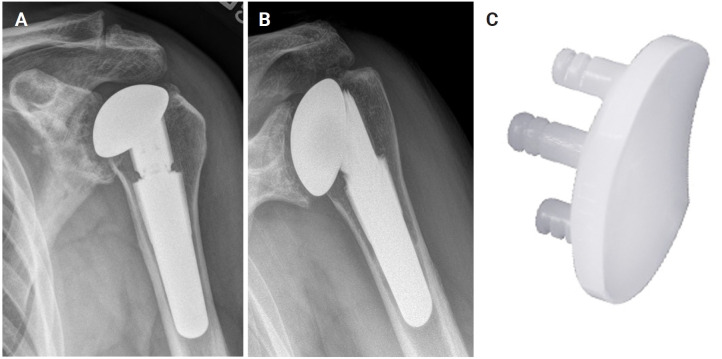

Abstract Image